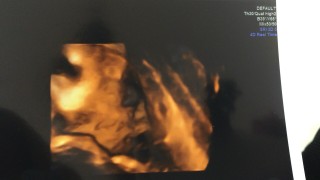

今日、検診に行って来ました! 体重は1992gだそうです! いつも4Dで顔を見る事が出来ず残念だったのですが、横顔が見れて嬉しかったです(^_^)目は線で書かれてしたいました!笑